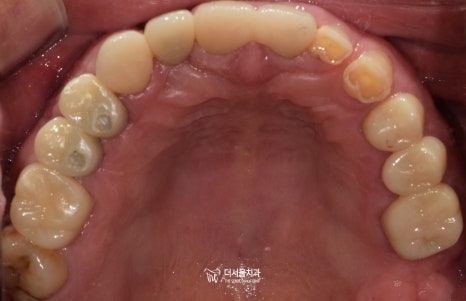

초진 구강 사진을 보면

곳곳에 이가 빠져서 빈 곳이 있고

남아있는 이들이 깨지고

벌어져있습니다.

환자께서는 전체적으로 상태가

안 좋은 것을 알지만

눈에 보이는 부분인 앞니만 해결

해 달라고 하셨습니다.

바로 어금니가 없기 때문입니다.

식사를 할 때 중축이 되는 대구치는

총 8개가 있어야 되는데요.

현재 3개밖에 남지 않았으며

맞물리는 이가 없어서

제 기능을 하지 못하고 있죠.